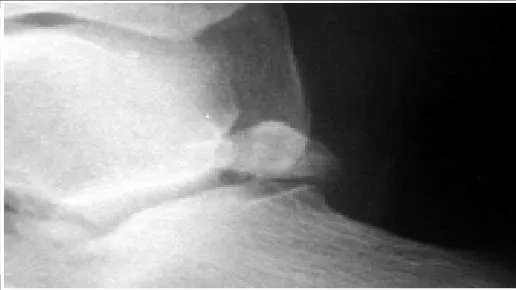

The structure that lies immediately medial to the bone prominence in the posterior ankle shown is the:

The os trigonum presented in the radiograph may be the cause of posterior ankle impingement. The flexor hallucis longus lies immediately medial to the os and must be protected during excision of this bone.